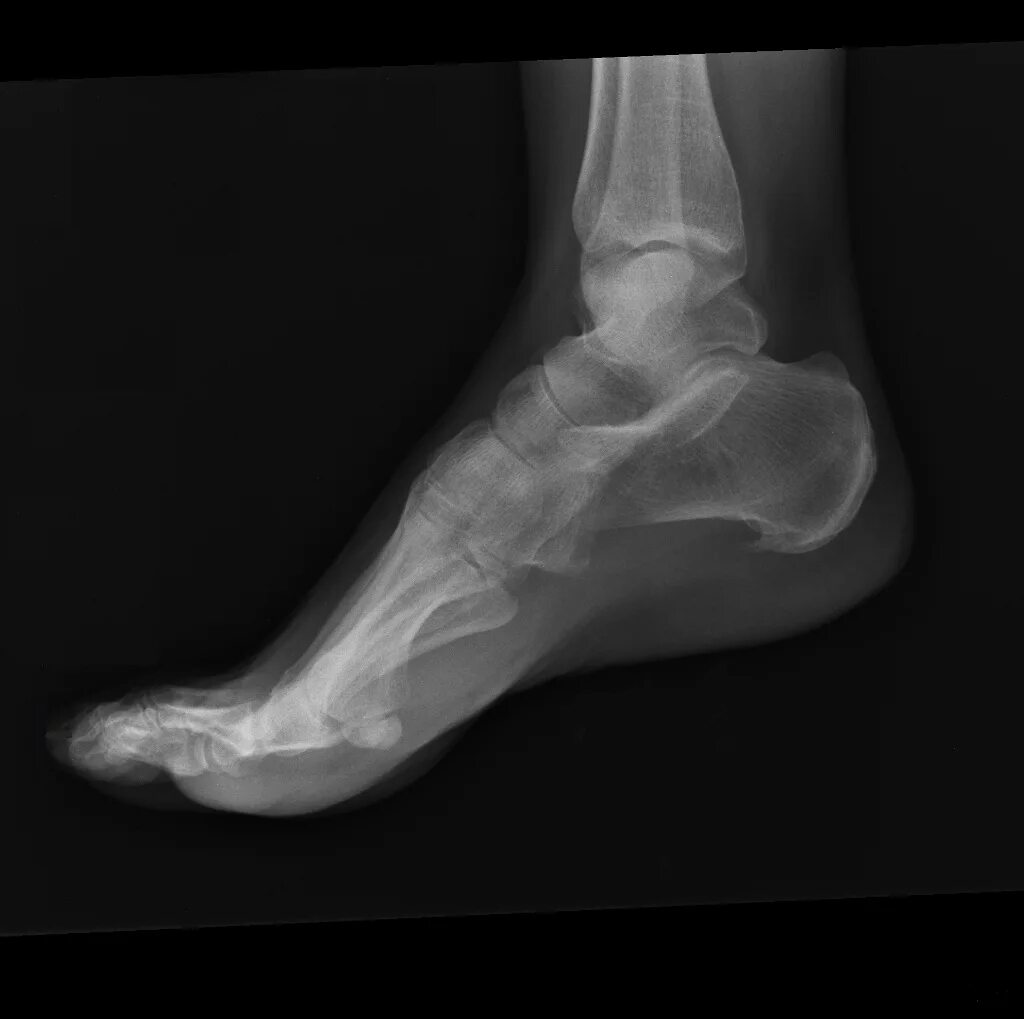

Пяточная шпора проходит сама по себе